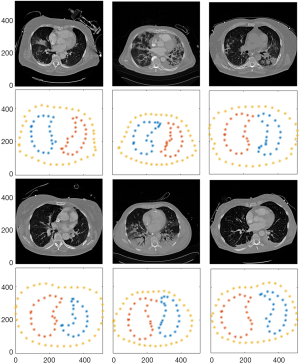

- Finite element forward model. The segmented thorax and lung contours were sampled to create extruded forward model (Figure 2) (19). The size of the thorax and lungs were normalized. The triangular meshing of the forward model is performed by Netgen software in order to obtain the finite element forward model. To ensure the accuracy of simulation, the number of finite elements of the forward model for all patients is larger than 20,000.

EIT image reconstruction and enhanced GI index calculation

Relative impedance changes of a breath were simulated by assigning different conductivities to the lungs in the forward model (Figure 2B). Two sets of boundary voltages were calculated, one for homogeneous background and one for highlighted lungs. The homogeneous ventilation distribution was reconstructed with the inverse model and the anatomically derived lung regions (Figure 2D) were identified with a threshold of 20% of the maximum impedance change (21). The corresponding GI index value GIsim,anat was calculated accordingly. With GIsim,anat we determined the lower limit of the GI measure for a homogenous distribution of ventilation.

Patient EIT measured data were reconstructed with inverse model and the functionally defined lung regions were identified (Figure 2F). The GI index was calculated based on the anatomically derived lung regions (GImeas,anat), which is the enhanced measure, and functionally derived lung regions (GImeas,func), which is the conventional approach.

Figure 2C and D shows the reconstructed image of the simulated homogeneous ventilation distribution of one patient, and the corresponding anatomically derived lung region. The reconstructed ventilation amplitude was not equaled between left and right lungs although the same amplitude was assigned to both lungs in the forward model (Figure 2C). The reconstructed image of the measured patient’s ventilation distribution and the corresponding functionally defined lung region could be found in Figure 2E and F. Non-ventilated regions could not be identified as lung regions using the latter approach. The sampling results of the thorax and lung contours from all patients are shown in Figure 3.